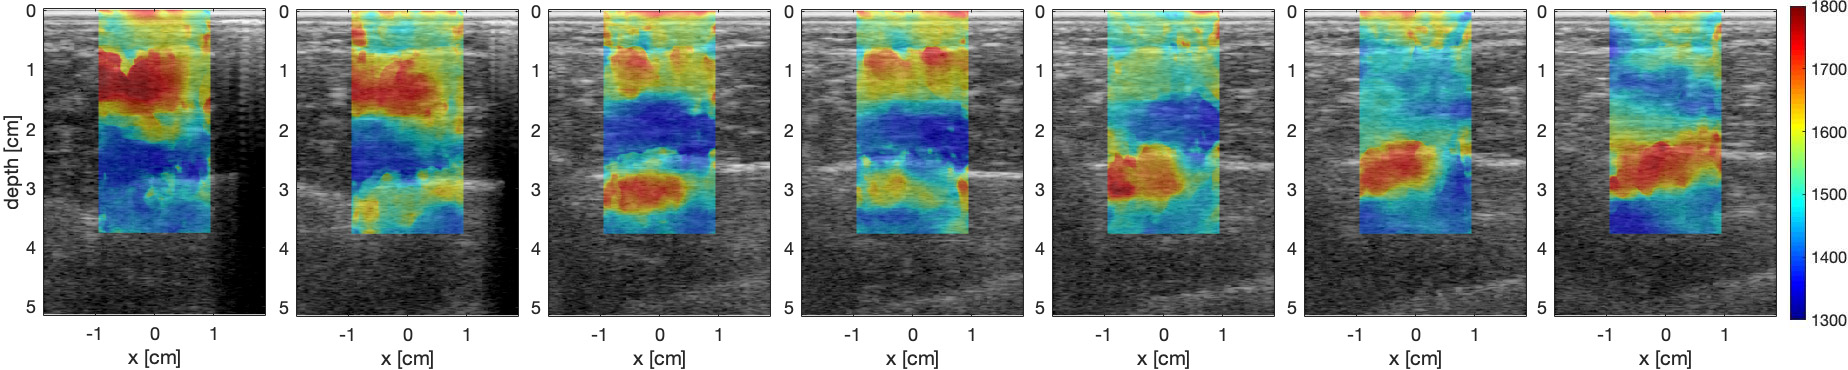

Fig. 4: Results for a squat maneuver. (a) shows the results for the transition from standing (left) to crouching (right) and (b) for the transition from crouching to standing position. Fig. 1(a) shows the location of the muscles in the frame. Blue denotes lower sound speeds, correlated with relaxed muscles, red denotes higher sound speeds, correlated with contracted muscles. Both cases show that the soleus (inside of the leg - bottom of the image) is doing most of the work in the crouching position while the gastrocnemius (outside of the leg - top of the image) is doing most of the work in the standing position.

Our experimental results are presented in Fig. 3, with Fig. 3(a) showing the response for the transition from standing to crouching (down phase) and Fig. 3(b) for the transition from crouching to standing. Red color denotes higher sound speeds that correlate with contracted muscle, while blue color denotes lower sound speeds, that correlate with relaxed muscle.

Results in both cases match the expected action. In the down phase, we see the task start with the GC (outside of the leg / top part of the image) with the soleus starting to activate on the third frame, and slowly transition to the soleus, where we see that the GS slowly relaxes and the soleus slowly contracts. On the up phase, we see the complementary behavior, where the work is initially carried out by the soleus, and slowly transitions to the GC.